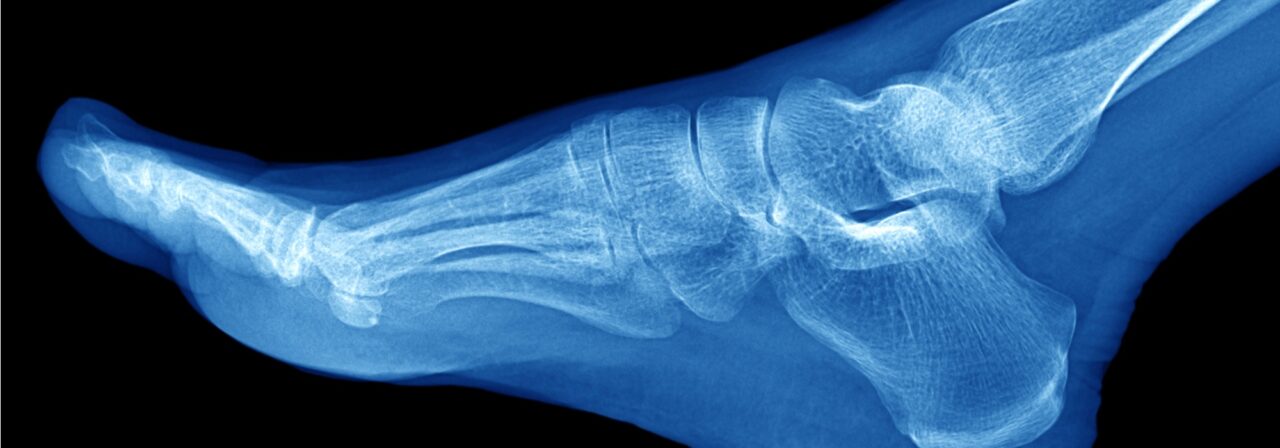

Otherwise know as "ankle arthroplasty," ankle replacement surgery is a technique that has developed in recent years in response to the need to effectively improve an ankle joint that has been severely damaged by injury or some form of arthritis. When other, more conservative methods of treating disabilities in the ankle have proven inadequate, joint replacement surgery may represent the best hope for long-term improvement to the ankle joint.

Both sides of the ankle are removed and replaced with specially designed artificial parts, called prostheses. The tibial prosthesis is made of medical- grade plastic with a titanium base plate tray that is inserted into the tibia and fibula. The talar component of the joint, the part that moves up and down, is replaced with a part made of cobalt chromium alloy, a metal commonly used in prostheses for other joints of the body also.